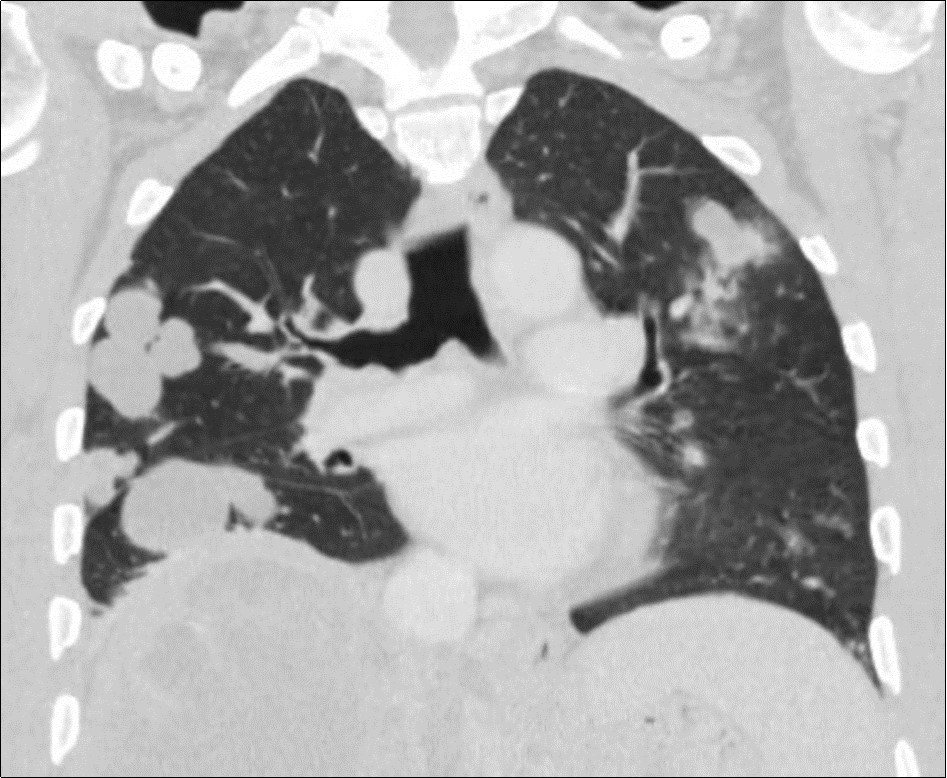

A 50-year-old man, was referred to our center for abdominal pain that had persisted for 1 month with marked loss of weight. An abdominal ultrasound completed by CT scan revealed a tumor of 15 centimeters of main axis of the right liver associated in contact with the portal vein associated with bilateral pulmonary nodules (Figure 1, Figure 2). Family and personal history for tuberculosis were negative. On admission, there was no fever, the abdomen was soft and non-tender, and there was a painful hepatomegaly without palpable mass. Blood showed anicteric cholestasis. Hydatid serology as well as tuberculin skin tests were negative. Upper and lower digestive endoscopy as well as tumor markers were normal. An ultrasound-guided fine-needle biopsy showednecro-inflammatory changes of the liver parenchyma without any signs of malignancy or specificity. Concerning the pulmonary lesions, there were no proof of active tuberculosis (sputum examination and bronchoalveolar lavage showed no BK). Patient received empiric antibiotherapy (amoxicillin and clavulanic acid) with regression of the pulmonary lesions in the control X Ray.

Figure 2.Coronal CT scan showing multiple bilateral pulmonary masses of both lungs associated with centrilobularmicronodules